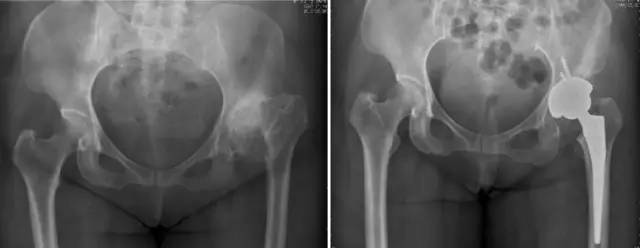

股骨头缺血性坏死

髋关节发育不良

强直性脊柱炎双髋强直

股骨颈骨折